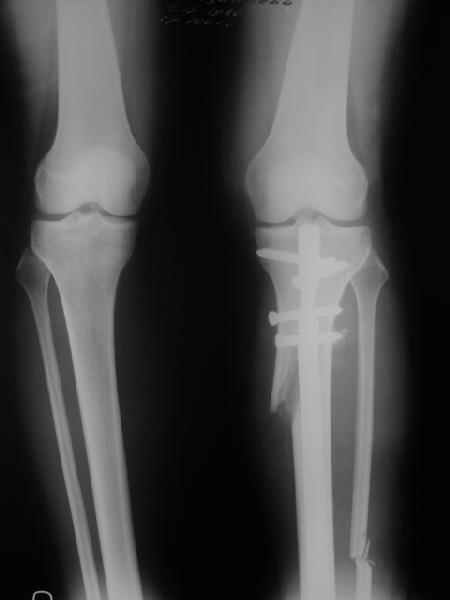

Re: Деформация голеней

Alexander Chelnokov 13 Сентябрь 2005, 23:23

Как уже писал, вчера сделал одну ногу (может, свой плюс будет что не обе- вдвое меньше травма, сразу на костыли встанет, оперированную ножку немного разомнет, тут и вторую заделаем).

Операция была интересной, много полезного опыта приобрел.

Снимки в приложении - фас сравнительный с неоперированной ногой. Жду критики.

Впрос про остеотомию большеберцовой непраздный. Эта получилась при надломе несколько более наклонно, чем я делал (сейчас проблема,

как на второй ноге сделать так же). Вот этот высоящий "зуб" центрального отломка не заменит ли в плане косметики то, что получается при медиализации дистального?

|

Отправитель: T. Derek V. Cooke 14 Сентябрь 2005, 18:23

Hi Alex:

Nice job!

It is very interesting to me that as you have derotated the tibia you have centred the patella, I think and the prox tibia looks much more anatomic.

The analysis in the attached images is direct, just using the tools.

Tibial tilt is perhaps more than you want but the tibial correction is to 90 (very slight over

correction.

Will need full length views to tell us about the hka but it appears neutral.

Measurements took 4 mins

Derek